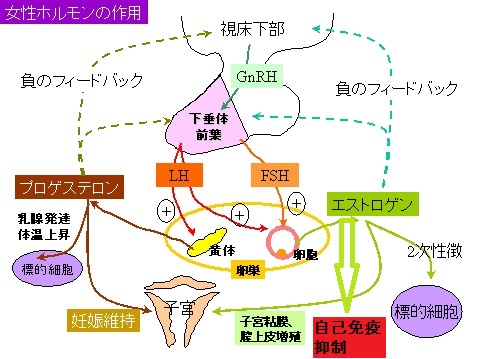

最初はゴナドトロピン(LH, FSH)分泌を刺激し、卵胞ホルモン(エストロゲン)を増加させますが、長期投与でGnRH 受容体の脱感作による反応低下(down-regulation)がおこり、逆に卵胞ホルモン(エストロゲン)は減少します。

- 最初は、放出されたゴナドトロピン(LH, FSH)が直接甲状腺を刺激。LH, FSHは弱いながらTSH(甲状腺刺激ホルモン)作用を持ちます

- 長期的には、甲状腺の自己免疫を誘発。卵胞ホルモン(エストロゲン)はステロイドホルモン属なので自己免疫を抑える作用があり、自己免疫性甲状腺疾患(橋本病, バセドウ病)の活動性は抑えられます。そして、卵胞ホルモン(エストロゲン)がジェットコースターのように頂上から急降下すると、抑えられていた自己免疫がリバウンドします。

以上から、

- 破壊性甲状腺炎(薬剤性無痛性甲状腺炎)誘発[元々、橋本病(慢性甲状腺炎)がある人に起こり易い]

- 甲状腺機能亢進症/バセドウ病誘発・悪化・再発

- 甲状腺機能低下症、粘液水腫性昏睡 誘発・増悪

黄体ホルモン剤(メドロキシプロゲステロン)高用量を投与すると、エストロゲン(卵胞ホルモン)合成・分泌が抑制され、エストロゲン依存性である乳がん・子宮がん細胞の増殖が抑えられます。

エストロゲン(卵胞ホルモン)が減少すれば、自己免疫性甲状腺疾患(橋本病, バセドウ病)の活動性を抑えられなくなり、薬剤性甲状腺中毒症が誘発される場合があります。(第56回 日本甲状腺学会 P2-076 酢酸メドロキシプロゲステロン投与により再燃したと考えられるバセドウ病の一例)